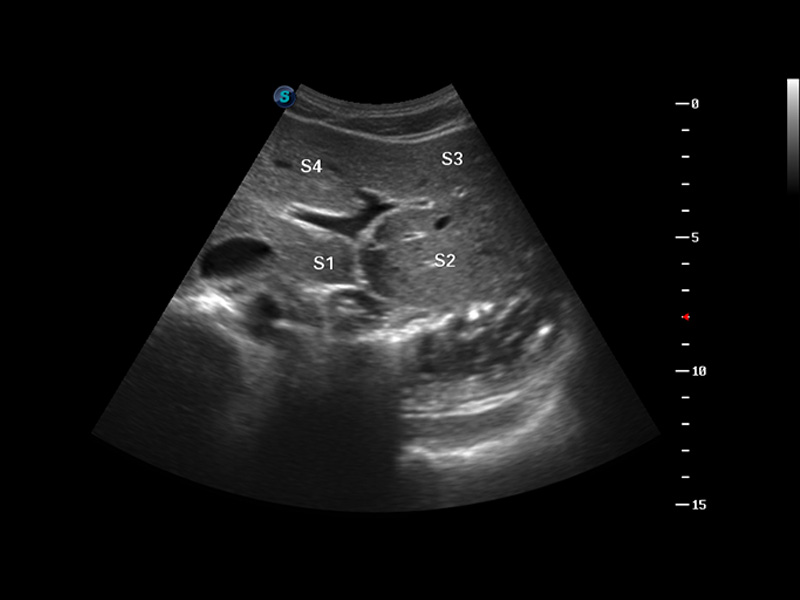

S8 EXP便携式彩色多普勒超声诊断仪是九州酷游研发的高端全身应用型便携彩超。高通道的VIS平台融合可视化(Visual)、智能化(Intelligent)和人性化(Smart)的特点,配以九州酷游自主研发生产的探头大家族,使您能够快速、准确的获得病人信息,提高工作效率的同时减轻疲劳。

3D/4D成像